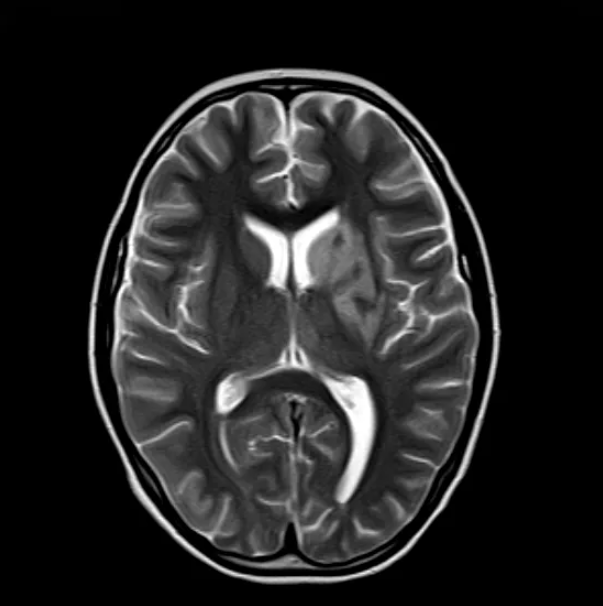

▲治疗前MRI

小小的症状立即引起了医生们的警觉,医院组织了儿科、神经外科、医学影像科等多学科专家进行联合会诊,最终被确诊为急性脑梗死——一种罕见于儿童但十分严重的疾病。

医护团队积极对小小实施抗凝治疗,防止脑血栓增大;实施抗炎治疗,减轻脑组织的损伤,改善脑循环,为小小受损的脑细胞提供营养。后期的康复训练则帮助她重获正常生活。